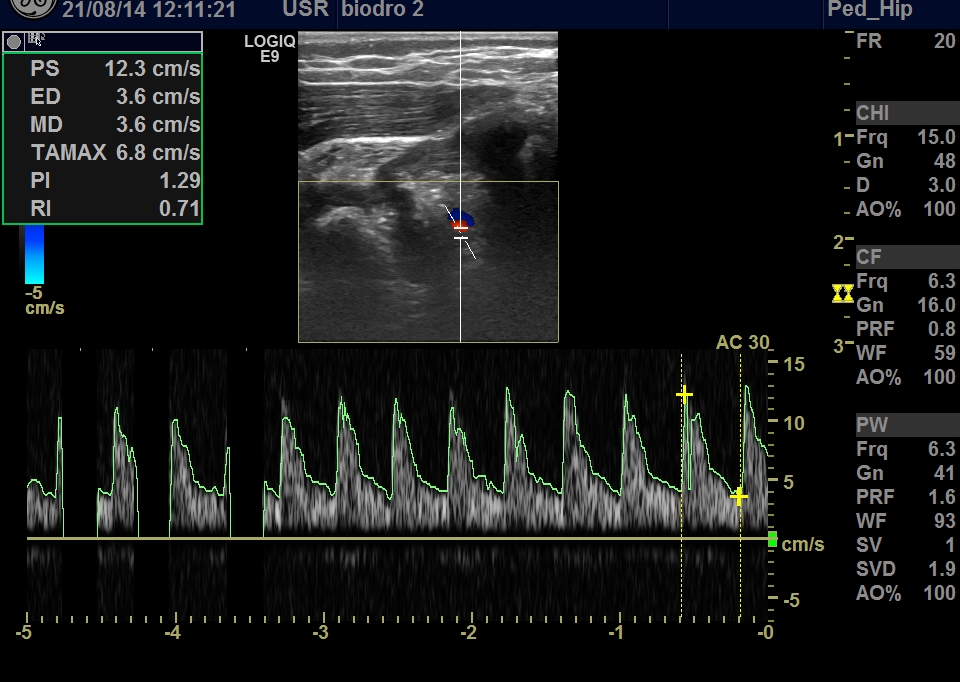

and we can check the blood supply by ultrasound doppler:

arteria cicumflexa medialis